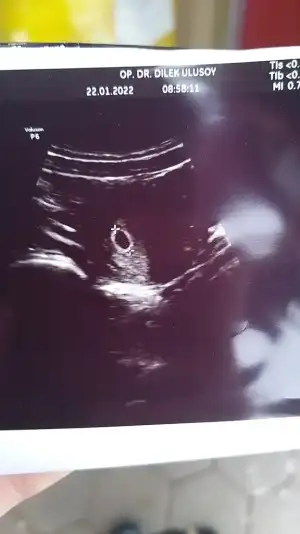

Selam kızlar bir şey soracağım pazartesi doktora gittiğimizde keseyi gördük ama bu yolk kesesi ne oluyor öyle bir şeyden bahsetmedi sanki aklıma takıldı 🤷‍♀️

Yook sac dedikleri bebeğin eşi , kese farklı plesenta dediğimiz. Doktor bebeği gösterirken yolk sac diye tanitiyor henüz yeniyse görünmeniz olabilir

Ben de ilk keseyi görmüştüm sadece. Kalp atışı için gittiğimde görmüştük yolk kesesini

Bende kalp atışı için gittiğimde soracağım bakalım doktorum çok detaylı anlatan birisi zaten olsa mutlaka anlatırdı henüz gözükmüyordur bendede

Off kızlar günler geçmiyor adet tarihim belli değil 9 ocaktan belli hamile olduğumu biliyorum ama kaç haftalik nedir ne değildir hiç bilmiyorum 26 ocakta randevum var artık iple çekiyorum kaç hafta olduğunu kesesi varmı kalbi atiyormu inanın çok merak ediyorum 🤧

• IMG-20220122-WA0001.webp

IMG-20220122-WA0001.webp

19,7 KB · Görüntüleme: 74